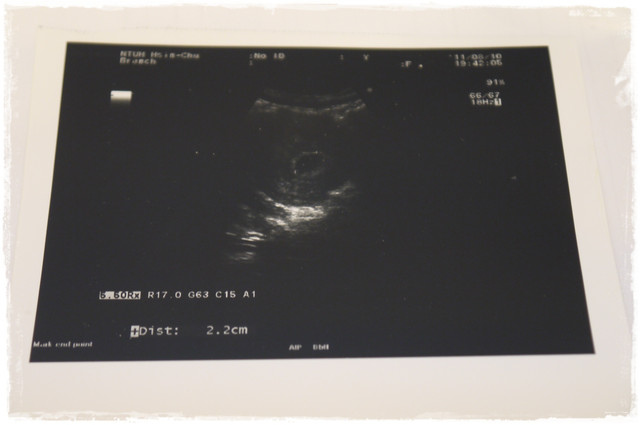

第二次檢查(2011.8.10):

1. Baby太小,聽不到強而有力的心跳。 Mi的狀況: 沒胃口但很嗜睡..

下次產檢: 兩週後,應該就可以聽到清楚的胎心音囉

檢查費用: 380元